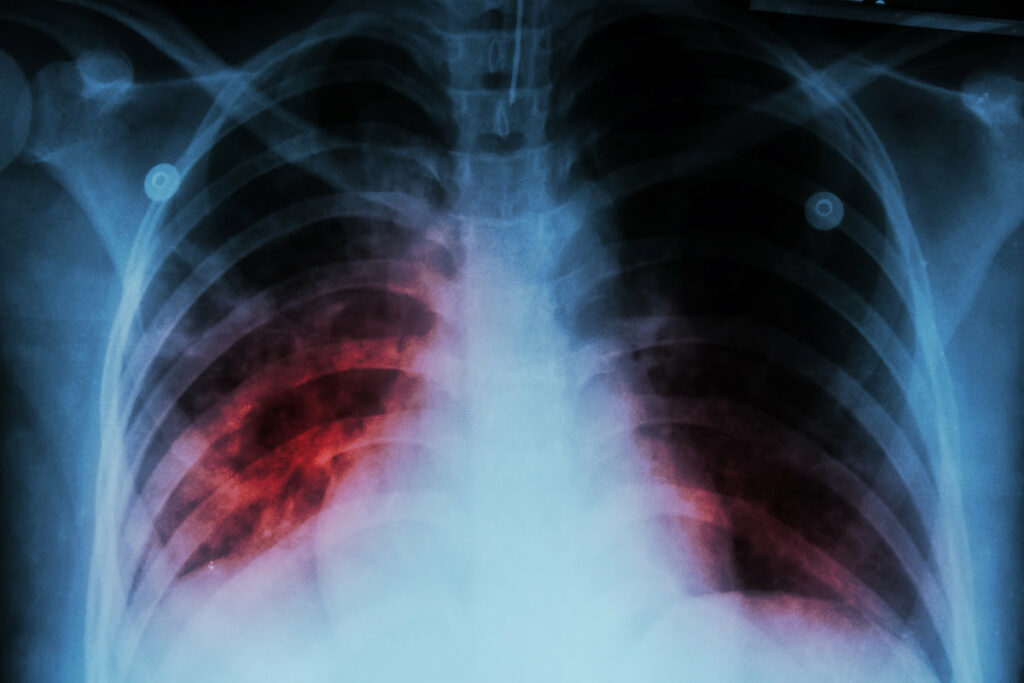

Environ 90 % des personnes infectées par la tuberculose ne développent pas la maladie. La tuberculose est alors asymptomatique (sans symptôme). La personne touchée par cette tuberculose dite latente n’est pas malade et ne transmet pas la maladie. Pour savoir si vous avez la tuberculose, votre médecin traitant vous prescrit une radiographie des poumons et le test de l’intradermoréaction (IDR) à la tuberculine. Ce test permet de savoir si vous avez été en contact avec le bacille de Koch.

La tuberculose, en se développant atteint plusieurs organes, notamment les poumons et les reins. Cette maladie infectieuse touche également les os, les ganglions, les neurones. Pour le Pr Pierre Delobel, «c’est un énorme problème de santé publique mondial, d’autant plus que le vaccin BCG ne protège que contre les formes graves chez l’enfant».